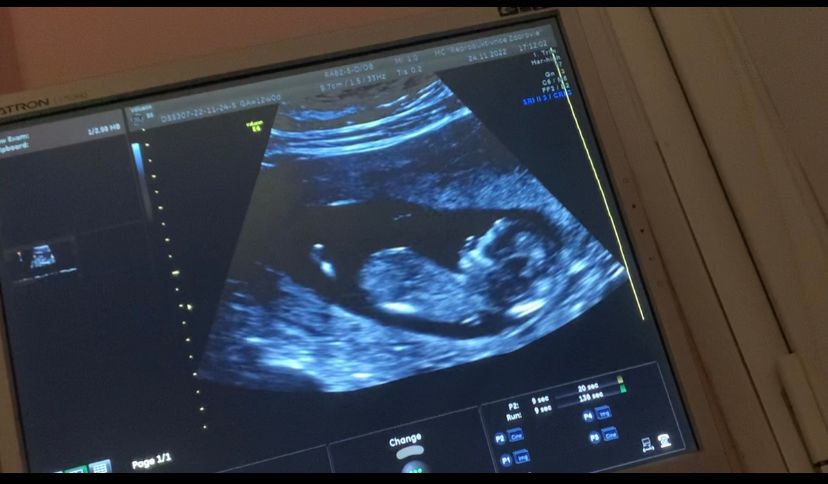

Потом зашли с мужем в кабинет, началось узи. Вижу своего малыша на экране, как он там развлекается и на сердце становится легче) Очень активный, крутился, вертелся, кувыркался, доктор с датчиком только успевал за ним)))

Итог - все у нас хорошо, развивается как положено, риски минимальные. Сказали следить за давлением(повышается риск преэклампсии к 37 неделе) и человек низковато прикрепился, но если его ничем не провоцировать, то и не страшно.

Пол - на 80% мальчик)

И по скринингу мы все таки больше на неделю из-за ранней овуляции.Так что 14 неделька уже пошла)